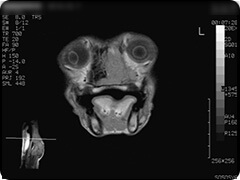

- 鼻腔内腫瘍

-

造影剤投与前

鼻腔内左側を占拠する病変。

右側にあるような正常な鼻甲介構造がなくなっています。

造影剤投与後

造影剤により強調されています。

組織生検による病理検査:鼻腔内神経芽腫疑い